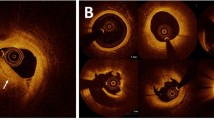

We visualized the attention of the slice-level and sequence-level transformer, which reflect the model’s attention within the slice and between the slices, respectively. The relative importance estimated by the model has been normalized between 0 (low) and 1 (high), and this estimated relative importance is visualized in accordance with a scale bar, as depicted in Fig. 2. As provided in the representative cases in Fig. 2, Supplementary Fig. S6, and Supplementary Videos S1 and S2, the DL model paid attention accurately to the lesion location compared to the ground truth annotation at the patient level. Within a single frame, the suspected culprit lesion was well localized by the model attention, suggesting that the model can identify the clinically important features within the given frame.

Plaque rupture and plaque erosion as seen on OCT, CTA, and CTA enhanced by DL model. Representative images of each label are shown. (A) shows an OCT image of plaque rupture. Plaque rupture is characterized by the presence of fibrous cap discontinuity with a cavity formation (asterisks) within the plaque. (A) also shows the residual ruptured cap (red arrow). (B,C) show CTA images of the corresponding site. (B) shows the ruptured cap (yellow arrow) protruding into the vessel lumen at the same site observed by OCT. (C) shows that the DL model attends on the ruptured cap and cavity. (D) shows an OCT image of plaque erosion. Definite plaque erosion is characterized by the presence of attached thrombus (blue arrow) overlying an intact and visualized plaque. (E,F) show CTA images of the corresponding site. (E) shows a small lumen surrounded by plaque without a cavity. (F) shows that the DL model attends on the site of stenosis without evidence of a cavity. In panels (C) and (F), the visualized model attention represents the relative importance as determined by the DL model for each specific image, with values normalized to a range between 0 and 1 for the images under consideration. CTA computed tomography angiography, DL deep learning, OCT optical coherence tomography, RI relative importance.